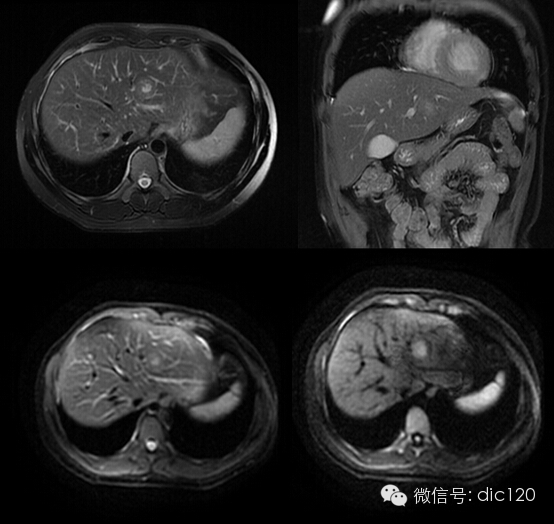

影像表現:CT平掃與正常肝組織呈等密度,密度均勻,動脈期病灶快速明顯均勻強化,中心見小片狀低密度影(瘢痕),門脈期及延遲期對比劑快速退出呈等密度,中央低密度影延遲強化。MRI腫塊T2WI為稍高信號,中央高信號。動態增強掃描動脈期均顯著增強,門脈期輕度增強,延遲期瘢痕強化。

FNH具有離心性血液供應及二條血液引流途徑。FNH的典型CT表現包括增強早期腫瘤呈彌漫均勻強化,在門靜脈期或門靜脈后期成等密度,病灶內可見中心低密度瘢痕及輻射狀分隔,腫瘤周圍有薄而不完整的包膜樣血管。瘢痕是FNH 另一個重要影像學表現,尤其是延遲掃描瘢痕強化為其特征。